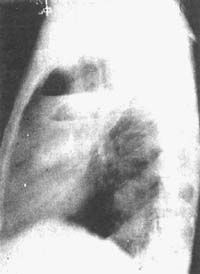

1.胸部X線檢查是肺膿腫的主要診斷方法。由於膿腫有向不同葉蔓延的特點,可波及多葉甚至全肺。但如一開始就發生在上述以外的部位,要懷疑有特殊的病因,如腫瘤堵塞性膿腫或肺囊腫感染等。肺膿腫在各不同階段病理改變很大,X線也有很大不同。急性期(在1周內)為大片緻密模糊陰影,按葉段分布呈楔形,尖向肺門,外側緊貼胸廓,縱隔或葉間胸膜面;在治療下,陰影改變較快。當膿腫與支氣管相通時,即出現空腔,由於引流支氣管多不通暢,加上體位因素,膿液不能完全排出,片上常見液平面。因壁厚,加上周圍仍有炎症,腔外有厚層,雲霧狀炎症浸潤影,慢性的周圍還有纖維化。空腔大小、形態不一,可呈圓形、橢圓形或不規則形,不少是多房的。經治療後如好轉,則空腔漸縮小、消失,留下纖維條索狀陰影及胸膜肥厚影。

(2)白細胞和中心粒細胞顯著增高。胸部X線特點為吸入性者不同時期呈大片狀、團塊形及空腔伴液平和其周圍有炎性陰影;血源性者為多發小片、雲團狀及張力性氣囊腫的炎性陰影。不同類型肺膿腫有其好發部位;